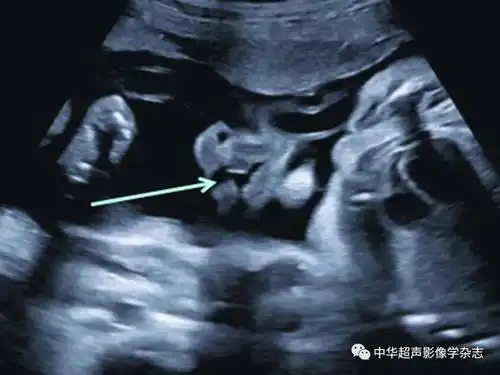

在妊娠20~24周超声检查时,应通过观察鼻唇冠状面判断上唇是否有唇裂